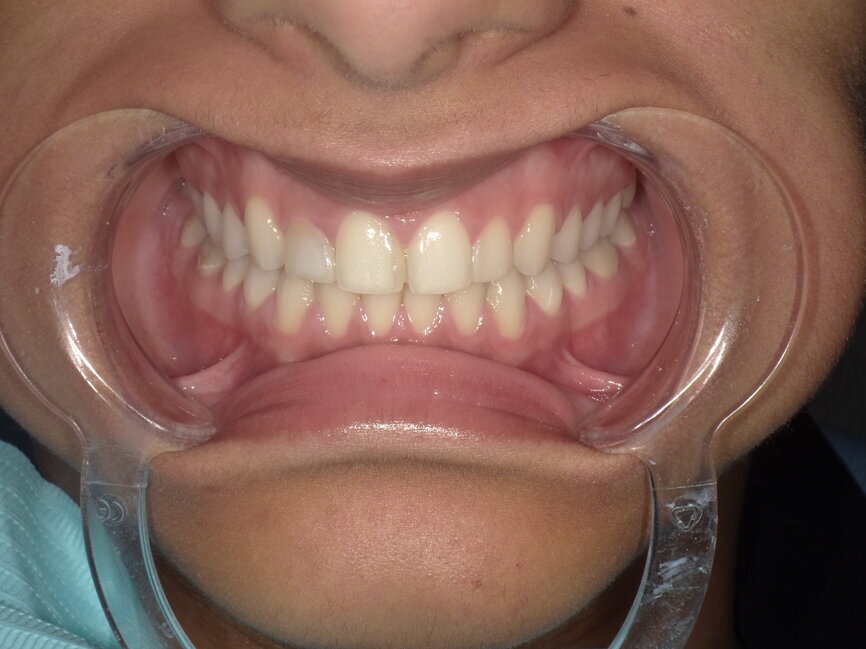

After the treatment planning discussion, the patient requested to proceed with direct resin-bonded composite veneers to enhance her smile. After the old composite fillings were removed (Fig 3, 4), smile design, was done to restore the golden proportion by modifying the shape and size of the teeth. Based on the smile design a mock-up was created to help obtain patient approval on the expected outcome and fabricate the silicone index.

Fig 4: Retracted view after removal of old restorations